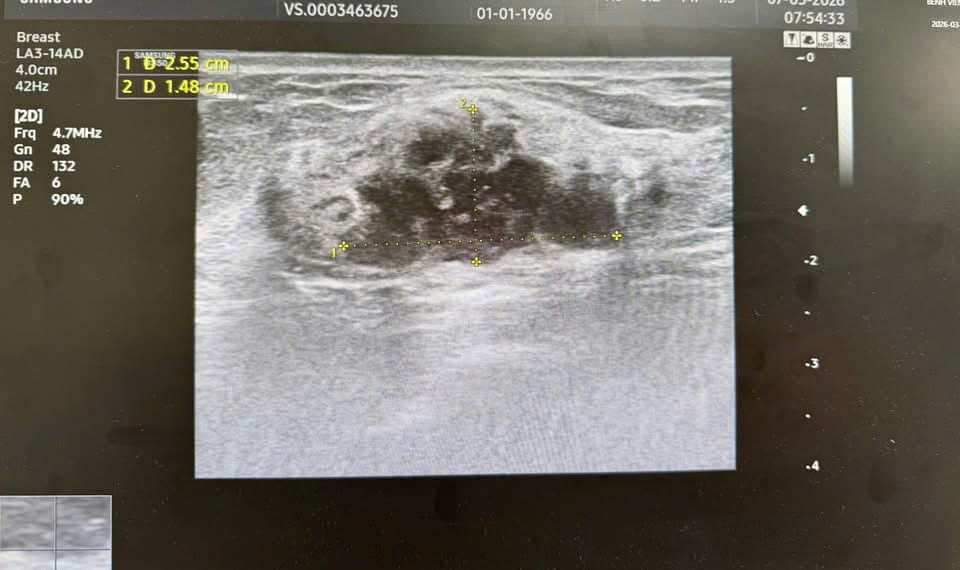

Trong suốt quá trình thăm khám, người bệnh không có bất kỳ triệu chứng bất thường nào: Không đau, không sờ thấy khối u, không có thay đổi trên da vùng vú. Tuy nhiên, nhờ kinh nghiệm lâm sàng và các phương tiện chẩn đoán chuyên sâu, bác sĩ đã phát hiện dấu hiệu bất thường nằm sâu trong mô tuyến vú:

Hình ảnh khối u được phân loại BIRADS 4 trên siêu âm và chụp X-quang tuyến vú.

Kết quả xét nghiệm tế bào học sau đó xác định người bệnh mắc ung thư biểu mô tuyến vú giai đoạn sớm.

Nếu không thực hiện kiểm tra định kỳ, khối u này rất khó phát hiện ở giai đoạn hiện tại.